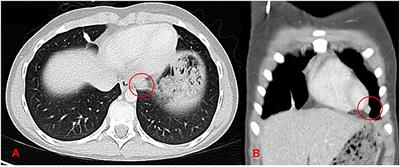

Interdisciplinary Radical “En-Bloc” Resection of Ewing Sarcoma of the Chest Wall and Simultaneous Chest Wall Repair Achieves Excellent Long-Term Survival in Children and Adolescents